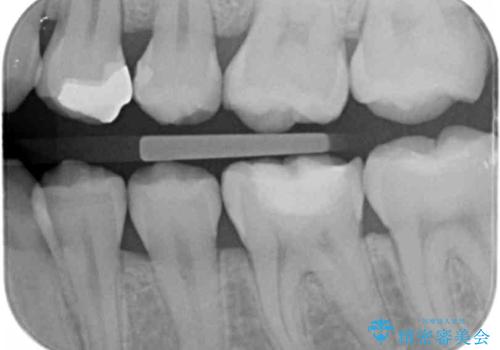

奥歯が樹脂の詰め物で継ぎ接ぎになっていることが確認されたため、今後の虫歯リスクを減らすために適合の良いフルジルコニアクラウンを入れていきます。

樹脂で継ぎ接ぎになった歯はそうでない歯と比べて虫歯になるリスクが高いです。

樹脂をすべて取り、虫歯も取り切った後に適合の良いクラウンを装着することで今後の虫歯リスクを減らすことができます。